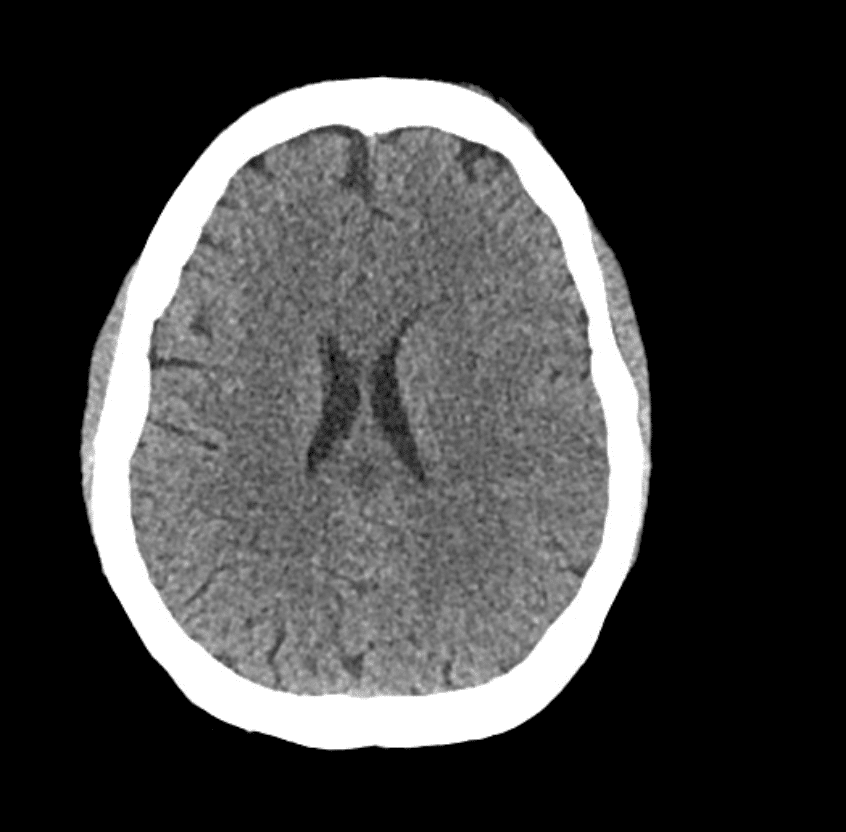

Vengono eseguiti una TAC cerebrale, un angiogramma e una scansione della perfusione cerebrale.

Descrivi e interpreta la TAC

Interpretazione della TAC